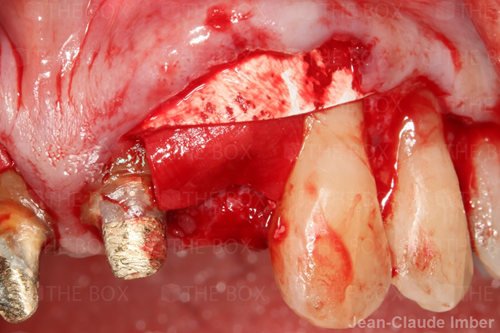

A new case was made public by Jean-Claude Imber check it out here.